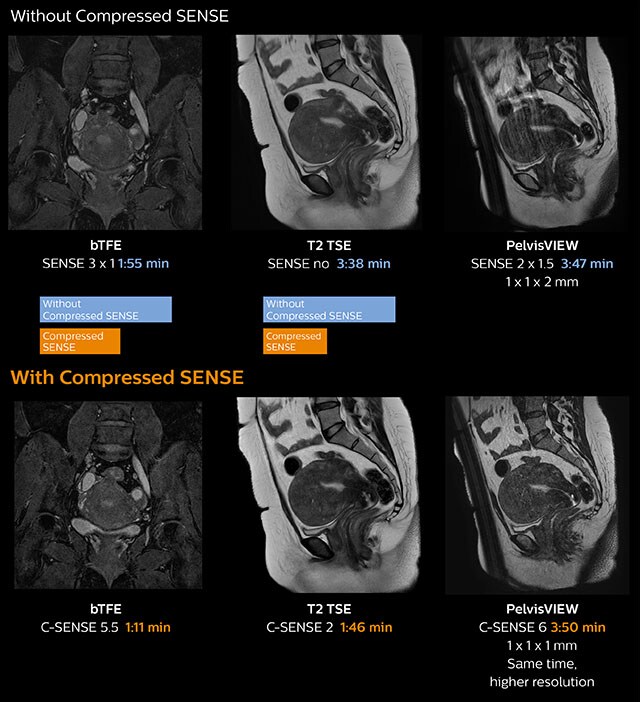

Up to 50% faster MRI scans with virtually equal image quality1

Philips Compressed SENSE is a cutting-edge MRI technology that significantly speeds up scans while delivering virtually equal image quality. By intelligently compressing data, it accelerates your existing MR scans by up to 50%, frees up time to improve your patient experience and can provide up to 60% higher resolution to enhance diagnostic confidence.1 Philips Compressed SENSE is suitable for all anatomies and can be used for all anatomical contrasts, in both 2D and 3D.

Demonstrated results of Compressed SENSE

1. 50%

faster scans with virtual equal image quality1

50%

so you can put the time you save to good use to address your capacity, scheduling and waitlist issues.

2. Up to 64%

higher spatial resolution within the same scan time1

Up to 64%

for example, to obtain high spatial resolution of tiny nerves and vessels for brain and spine examinations.

Compressed SENSE enables acceleration by up to 50% with the same resolution and virtually equivalent image quality as dS SENSE scanning. The time saved can boost productivity by enabling more patients per day.

Compressed SENSE can be used to create images with higher resolution in the same scan time that is currently allotted for exams to increase diagnostic confidence.